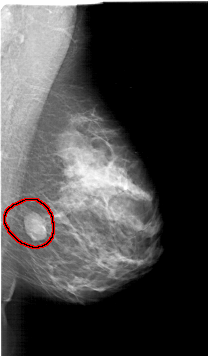

A_1394_1.LEFT_MLO

LEFT_MLO LINES 5926 PIXELS_PER_LINE 3676 BITS_PER_PIXEL 12 RESOLUTION 43.5 NON_OVERLAY

FILE: A_1394_1.RIGHT_MLO.OVERLAY

TOTAL_ABNORMALITIES 1

ABNORMALITY 1

LESION_TYPE MASS SHAPE LOBULATED MARGINS CIRCUMSCRIBED

ASSESSMENT 4

SUBTLETY 5

PATHOLOGY BENIGN

TOTAL_OUTLINES 1

BOUNDARY